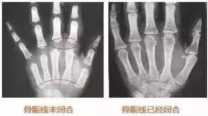

那么什么是骨骺线呢?看完下面这张图,你肯定能明白。

孩子在婴幼儿时期,长骨的骨干和骨骺之间,存在一个软骨带。在X线片中,显示为分离间隙,这个间隙正是为骨骼伸长预留的空间。

青春期结束后,这个软骨带将钙化成一段白线,也叫“成长线”,标志着骨干和骨骺彻底融合,长骨伸长结束,孩子的个子也就不会再长高了。